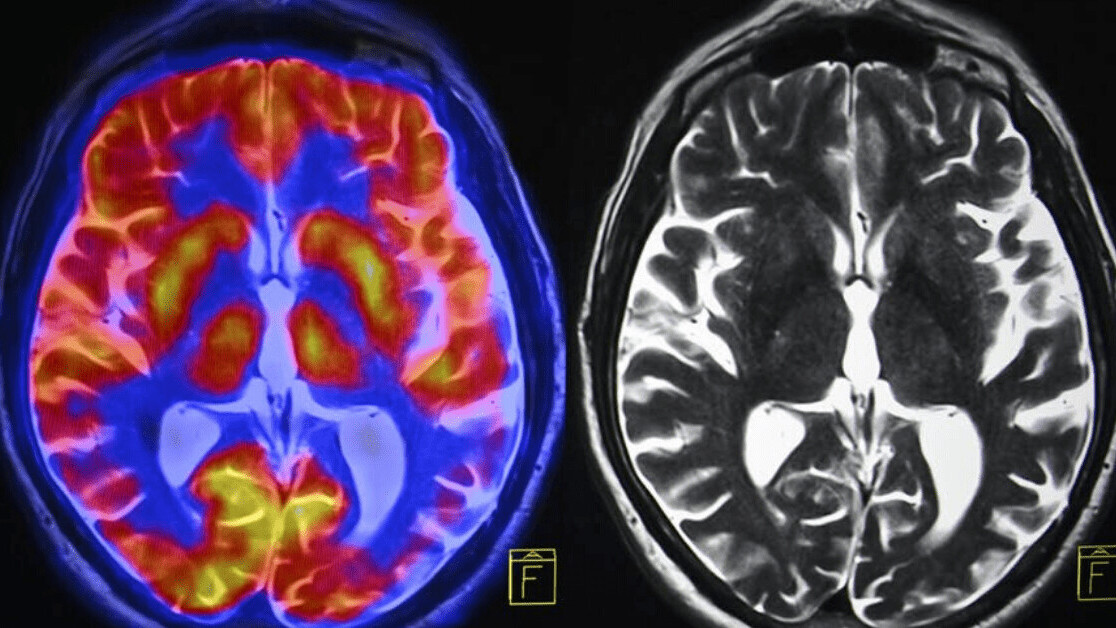

The brain’s hippocampus is a critical brain region for learning and memory, and is particularly vulnerable to such insults. Studies in humans have shown that inflammation can adversely affect brain systems linked to motivation and mental agility.

There is also evidence of chronic stress effects on hormones in the brain, including cortisol and corticotropin releasing factor (CRF). High, prolonged levels of cortisol have been associated with mood disorders as well as shrinkage of the hippocampus. It can also cause many physical problems, including irregular menstrual cycles.

There are many reasons for this, and they can be linked to changes in the brain. The reduced hippocampus that a persistent exposure to stress hormones and ongoing inflammation can cause is more commonly seen in depressed patients than in healthy people.